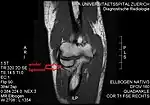

Capsule of elbow-joint (distended). Anterior aspect.

Annular ligament of radius, from above. The head of the radius has been sawn off and the bone dislodged from the ligament.